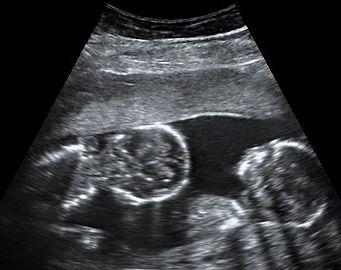

Dichorionic-diamniotic twins at 8 weeks and 5 days since co-incubation as part of IVF. The twin at left in the image is shown in the sagittal plane with the head pointing towards upper left. The twin at right in the image is shown in the coronal plane with the head pointing rightwards.